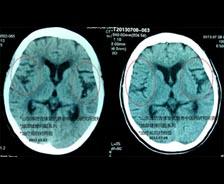

| 阿尔茨海默病(老年痴呆症)典型病例 |

| 于2014年4月13日再随访,患者李XX非常健康的照片 李XX,男,62岁,农民,山东烟台人,1996年12月21日初诊。患者儿子述:一年前因家务事出现情绪不佳,渐渐面无表情不爱说话,忘事渐渐加重,外出时忘记家门不能自己回家,晚上睡眠较少,近3个月病情加重,忘... [ 查看详情 ] |

| 标题:脑萎缩典型病例 |

| 简介:庄XX,女,67岁,退休干部。2013年5月2日下午3点就诊。病情:主诉右侧上下肢麻木、有时出现活动无力已2月余,近5天明显加重。患者两年多来经常头晕不适,长期失眠,记忆力逐渐减退,近两个多月来出现右侧上下肢麻木、有时活动无力,有时行走时摔倒... [ 查看详情 ] |